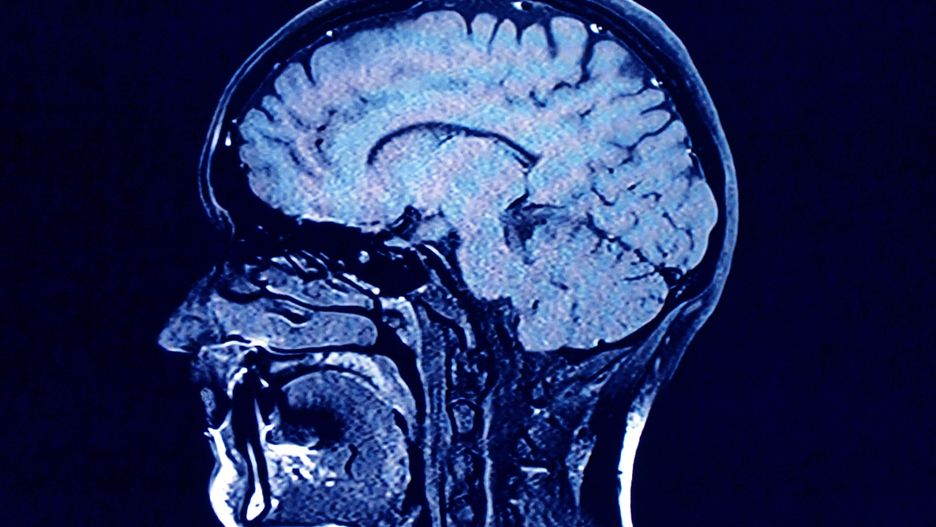

Badania nad wpływem koronawirusa na ludzki organizm trwają na całym świecie. Uczeni z Lewis Katz School of Medicine na Temple University przedstawili wyniki swojej pracy. Sprawdzili między innymi, czy koronawirus może mieć wpływ na mózg zakażonego pacjenta.

Naukowcy zwracają uwagę na problemy neurologiczne występujące u zakażonych. Jak pisze serwis Science Daily, chodzi o zawroty i bóle głowy, utratę węchu i problemy z koncentracją. Istnieje możliwość, że koronawirus atakuje komórki układu nerwowego, jednak nie ma jeszcze niezbitych dowodów na potwierdzenie tej tezy.

Badania pozwoliły dokonać kolejnego odkrycia. Chodzi o białko szczytowe wirusa. Pobudza ono odpowiedź zapalną w komórkach, które tworzą barierę krew-mózg. Naukowcy ustalili, że koronawirus może osłabić tę barierę i następnie zaatakować mózg, komórki i połączenia nerwowe.

Wyniki naszych badań dowodzą, że koronawirus SARS-CoV-2 lub jego białka szczytowe, które krążą swobodnie w krwiobiegu, mogą prowadzić do destabilizacji bariery krew-mózg w bardzo istotnych regionach mózgu - powiedział Servio H. Ramirez z Lewis Katz School of Medicine w Temple University, który przewodził zespołowi prowadzącemu badania.

Jakie mogą być długofalowe skutki zmienionej bariery krew-mózg u osób, które są zakażone koronawirusem? Tego dokładnie nie wiadomo

Są jednak powody do niepokoju. Współautorka badania, dr Tetyana P. Buzhdygan, wyjaśnia, że układ naczyniowy mózgu jest bardzo rozgałęziony, w związku z czym nawet małe ognisko procesu zapalnego może być szkodliwe dla tkanki nerwowej.